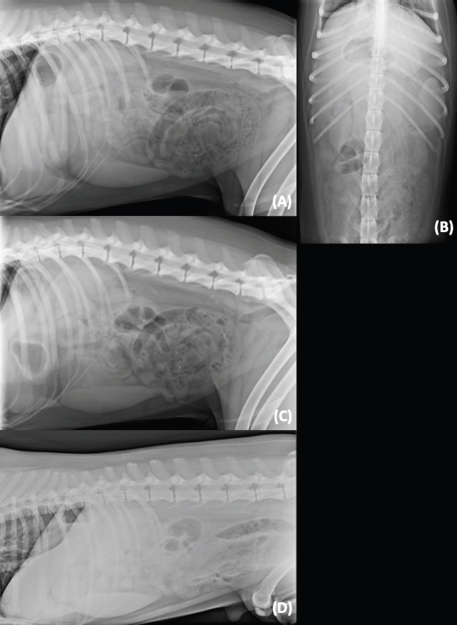

It is reported that normal small intestinal loops are usually diffusely distributed in the abdominal cavity with a smooth round turn, appearing as continuously curving tubes or as solid circles or rings (Thrall, 2013). In cases of mechanical ileus, the intestinal loops become progressively distended, the segments become crowded into a relatively smaller space, often assuming a stacked appearance (Thrall, 2013). In this study, the use of the HB view did not affect the visualization of small intestinal disposition compared with the VB views, thus a different recumbency seems not to alter the small intestinal disposition. However, organs crowding at the ventral aspect of abdomen make it difficult the evaluation of fluid/soft tissue filled intestines when there is concurrent peritoneal effusion due to border effacement of structures (Fig. 3).

Fig. 3. Example of crowding organs at the ventral aspect of the abdomen in a left-to-right lateral HB view. Evaluation of the ventral abdomen is challenging due to presence of fluid/soft tissue-filled intestines and concurrent peritoneal effusion.